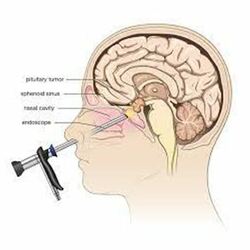

Pituitary Adenoma

A pituitary adenoma a small growth or tumour on the pituitary gland. It is benign (noncancerous) Unlike cancer, it doesn’t spread to other parts of your body. But as pituitary adenomas grow, they can put pressure on nearby structures and cause symptoms like

What is the pituitary gland?

Your pituitary is a small gland about the size of a pea that’s joined to your hypothalamus (the base of your brain) right behind your nose. It has two lobes: the anterior (front) lobe and the posterior (back) lobe. Each lobe releases different hormones. Hormones are chemicals that coordinate different functions in your body by carrying messages through your blood to your organs, muscles, and other tissues.